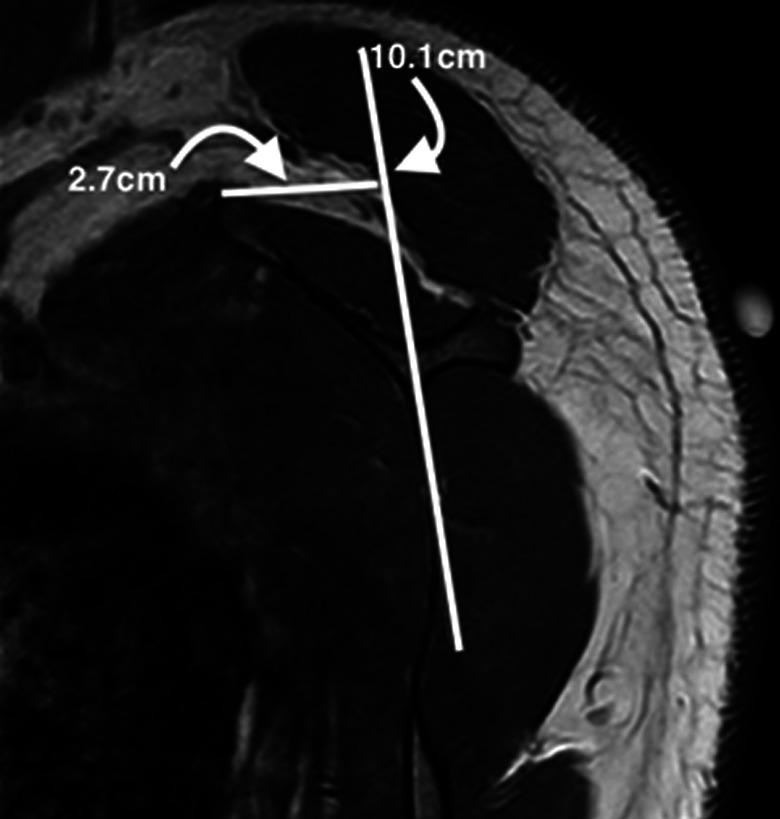

A total of 8 patients underwent arthroscopic scapular debridement and bursectomy; 5 of the 8 patients underwent additional medial scapulectomy. There were 5 male (62.5%) and 3 female (37.5%) patients with a mean age of 30.1 ± 12.3 years (range, 19-58 years). Inclusion criteria for surgery were patients with symptomatic scapulothoracic bursitis for whom extensive nonoperative modalities had been utilized for at least 6 months but failed. Outcome measures included the Oxford Shoulder Score (OSS), University of California Los Angeles (UCLA) shoulder rating scale, Constant Shoulder Score (CSS), and visual analog scale (VAS) for pain. The bony parameters included scapular shape, anterior offset, costomedial angle, and medial scapular corpus angle (MSCA).

The follow-up duration was at least 2 years for all patients (mean follow-up, 25.0 ± 4.1 months [range, 24-35 months]). The majority of patients had a concave-shaped scapula (62.5%). The mean anterior offset was 24.3 ± 3.4 mm, and the mean costomedial angle was 132.3° ± 9.6°. Half the patients had a positive MSCA, while the other half had a negative MSCA. A statistically significant improvement was observed in the OSS, UCLA, CSS, and VAS scores from preoperatively to 2-year follow-up ( < .001 for all). No complications were observed.